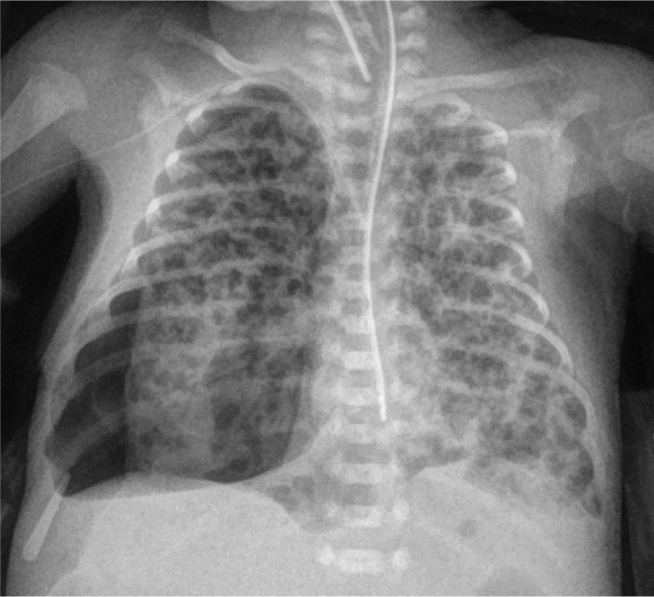

Case report: We present a case of an extremely preterm infant with persistent PTX who was successfully treated with fibrin glue. In addition, we present a two-and-a-half-year corrected age follow-up focusing on respiratory problems, motor development and sensory organs. Furthermore, we touch upon the related ethical issues.

Conclusions: Fibrin glue should be used to treat persistent PTX even in an extremely preterm infant. No adverse effects were observed. At the two-and-a-half-year corrected age follow-up, despite severe bronchopulmonary dysplasia development, no serious pulmonary problems were observed. However, the child's development is uncertain. This situation raises important ethical issues concerning saving the lives of infants at the limit of viability.